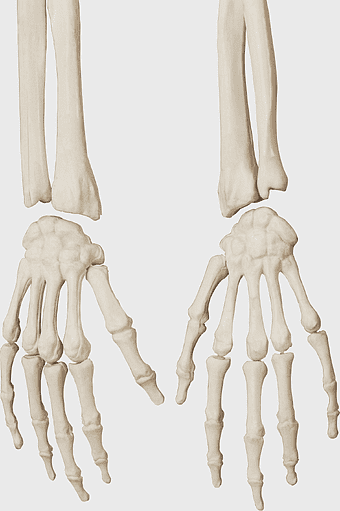

gray hand bone illustration, Human skeleton Hand Drawing Bone, carpal bones anatomy, monochrome palm skeleton, skeletal hand structure, human hand bones diagram, medical illustration hand -

skeleton hands, human anatomy, carpal bones, ulna bone, digital medical illustration, skeletal structure, bony appendages detailing -